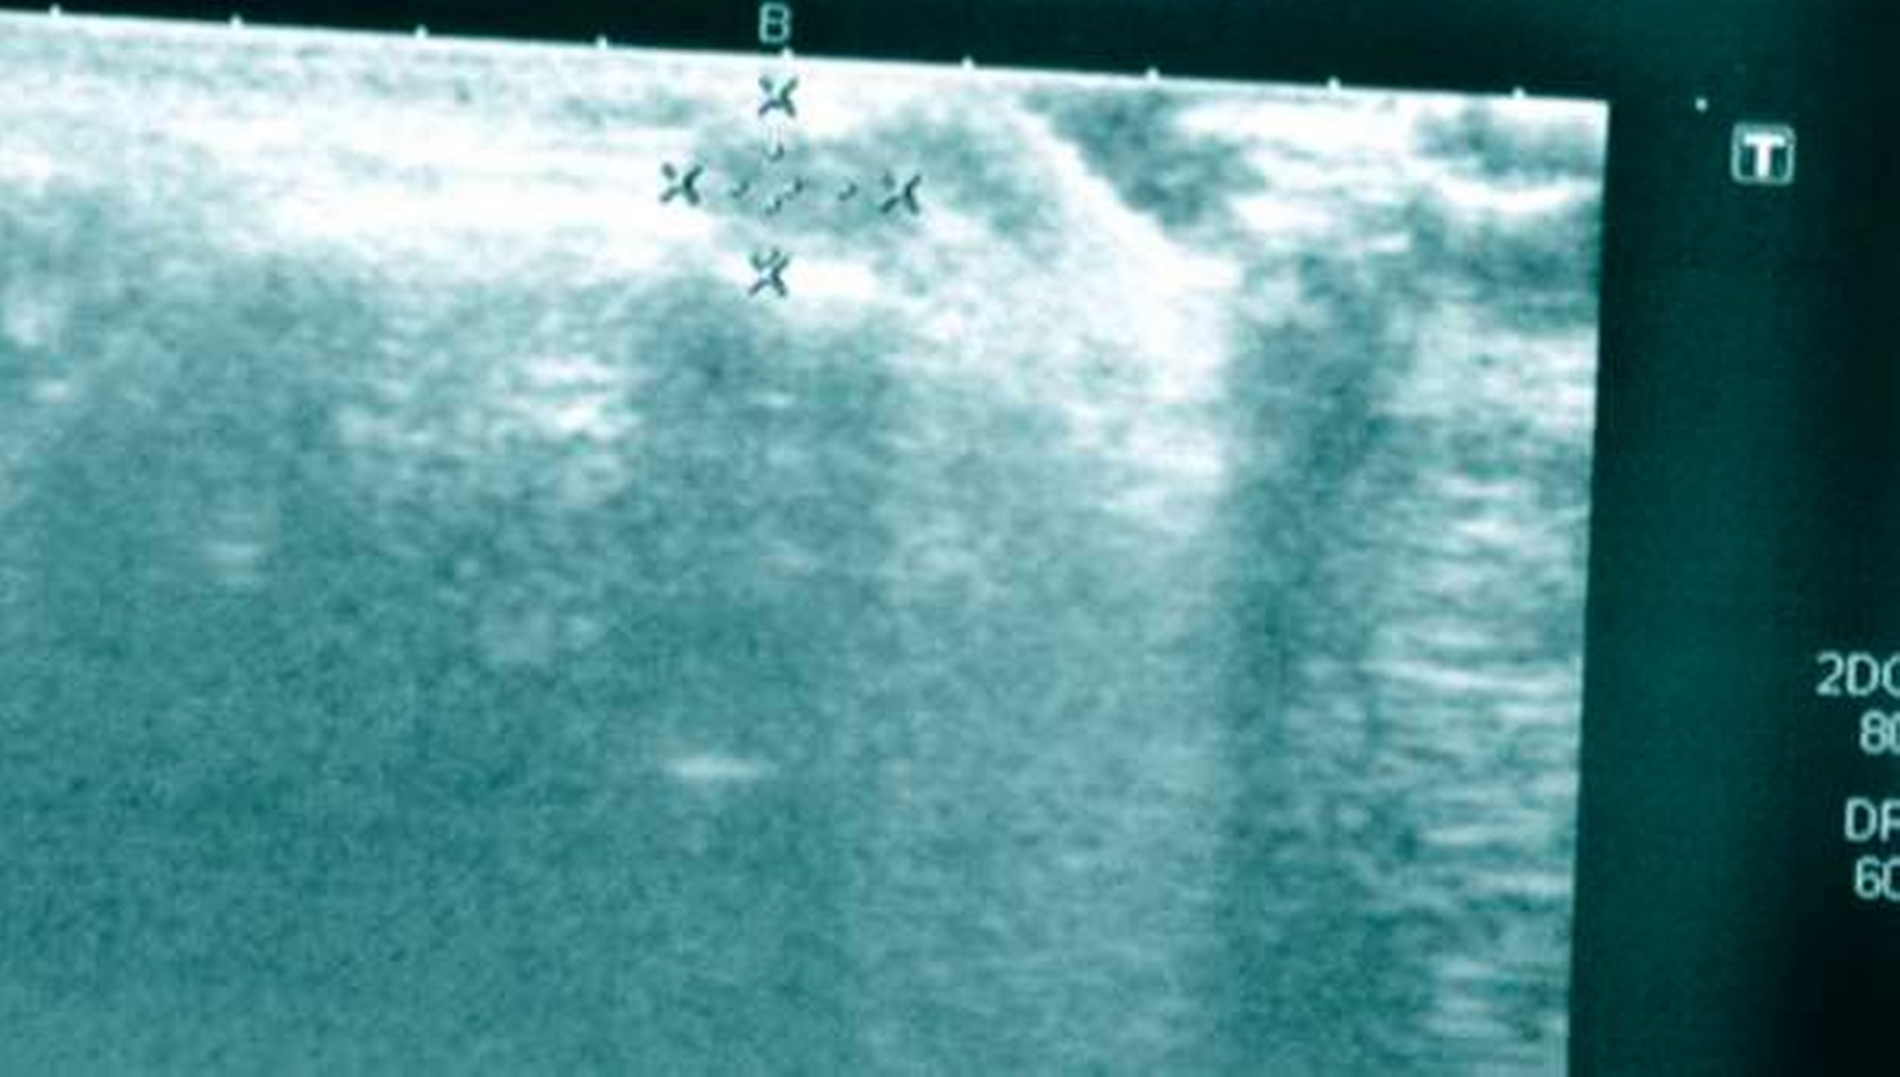

Sonografisch konnte ein mit einer Kapsel umgebener, nicht infiltrierend wachsender, inhomogener Tumor mit dorsalem Schallschatten nachgewiesen werden (Abbildung 1). Gemeinsam mit den Eltern wurde entschieden, eine MRT-Untersuchung in Intubationsnarkose durchzuführen und anschließend – bei Bedarf in derselben Narkose – die anscheinend benigne Raumforderung zu entfernen.

Zysten der Weichteile werden im Allgemeinen an ihrem klinischen Aussehen, an ihrer Lokalisation und an ihren Symptomen erkannt. Ihr Ursprung kann traumatisch oder entwicklungsbedingt sein. Sie erscheinen normalerweise als schmerzlose Schwellung mit Ausdehnung in die angrenzenden Weichteile. Die Konsistenz der Läsion wird zuerst durch Palpation untersucht, während für weitere Informationen – wie im vorliegenden Fall – ein Ultraschall sinnvoll ist. Abschließend kann ein CT oder MRI einen detaillierteren Blick auf die Läsionsränder erlauben.